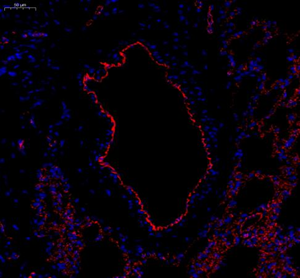

| IF analysis of CD31 (GB12063). Sample: Rat lung (Paraffin), 4% PFA (G1101) 12-24h. Antigen retrieval: Citrate buffer (pH 6.0) (G1201), pressure cooker 2min. Blocking buffer: 3% BSA in PBS (GC305010), RT, 30min. Primary antibody: 1: 600, 4°C overnight. Secondary antibody: Cy3 conjugated Goat Anti-mouse IgG (H+L)(GB21301),1: 200 RT 1h. |

| IF analysis of CD31 (GB12063). Sample: Rat lung (Paraffin), 4% PFA (G1101) 12-24h. Antigen retrieval: Citrate buffer (pH 6.0) (G1201), pressure cooker 2min. Blocking buffer: 3% BSA in PBS (GC305010), RT, 30min. Primary antibody: 1: 600, 4°C overnight. Secondary antibody: Cy3 conjugated Goat Anti-mouse IgG (H+L)(GB21301),1: 200 RT 1h. |